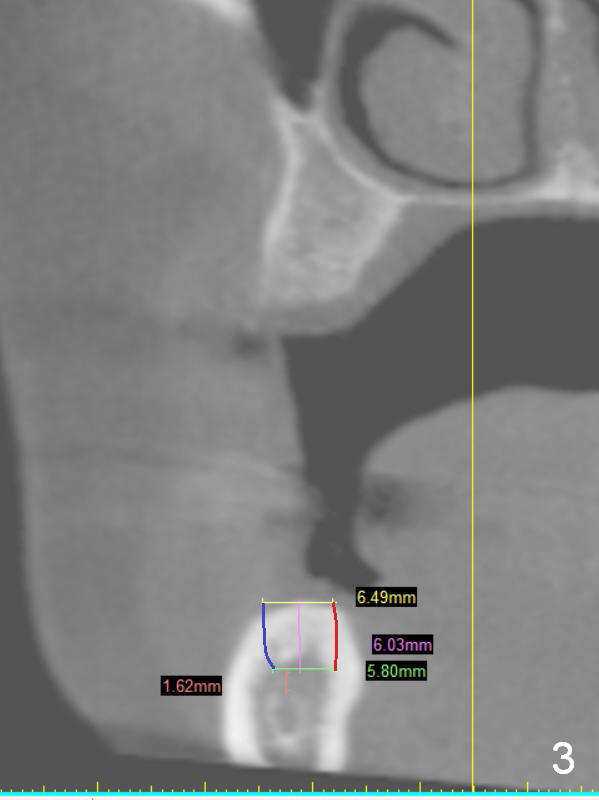

A 49-year-old lady is petit. The crest at #30 is narrow. A small implant is placed. To increase its longevity, the patient should have left 1st molar occlusion. Bone density at #19 is D1 (the cortex), D4 (upper medulla) and D3 (lower medulla) (Fig.1). Bone is wide enough to hold a 6 mm (in diameter) implant, but a 8 mm long implant appears to be too long (Fig.2). Therefore, a 6 or 6.5x6 mm implant appears to be appropriate (Fig.3). How about the bone at #14?